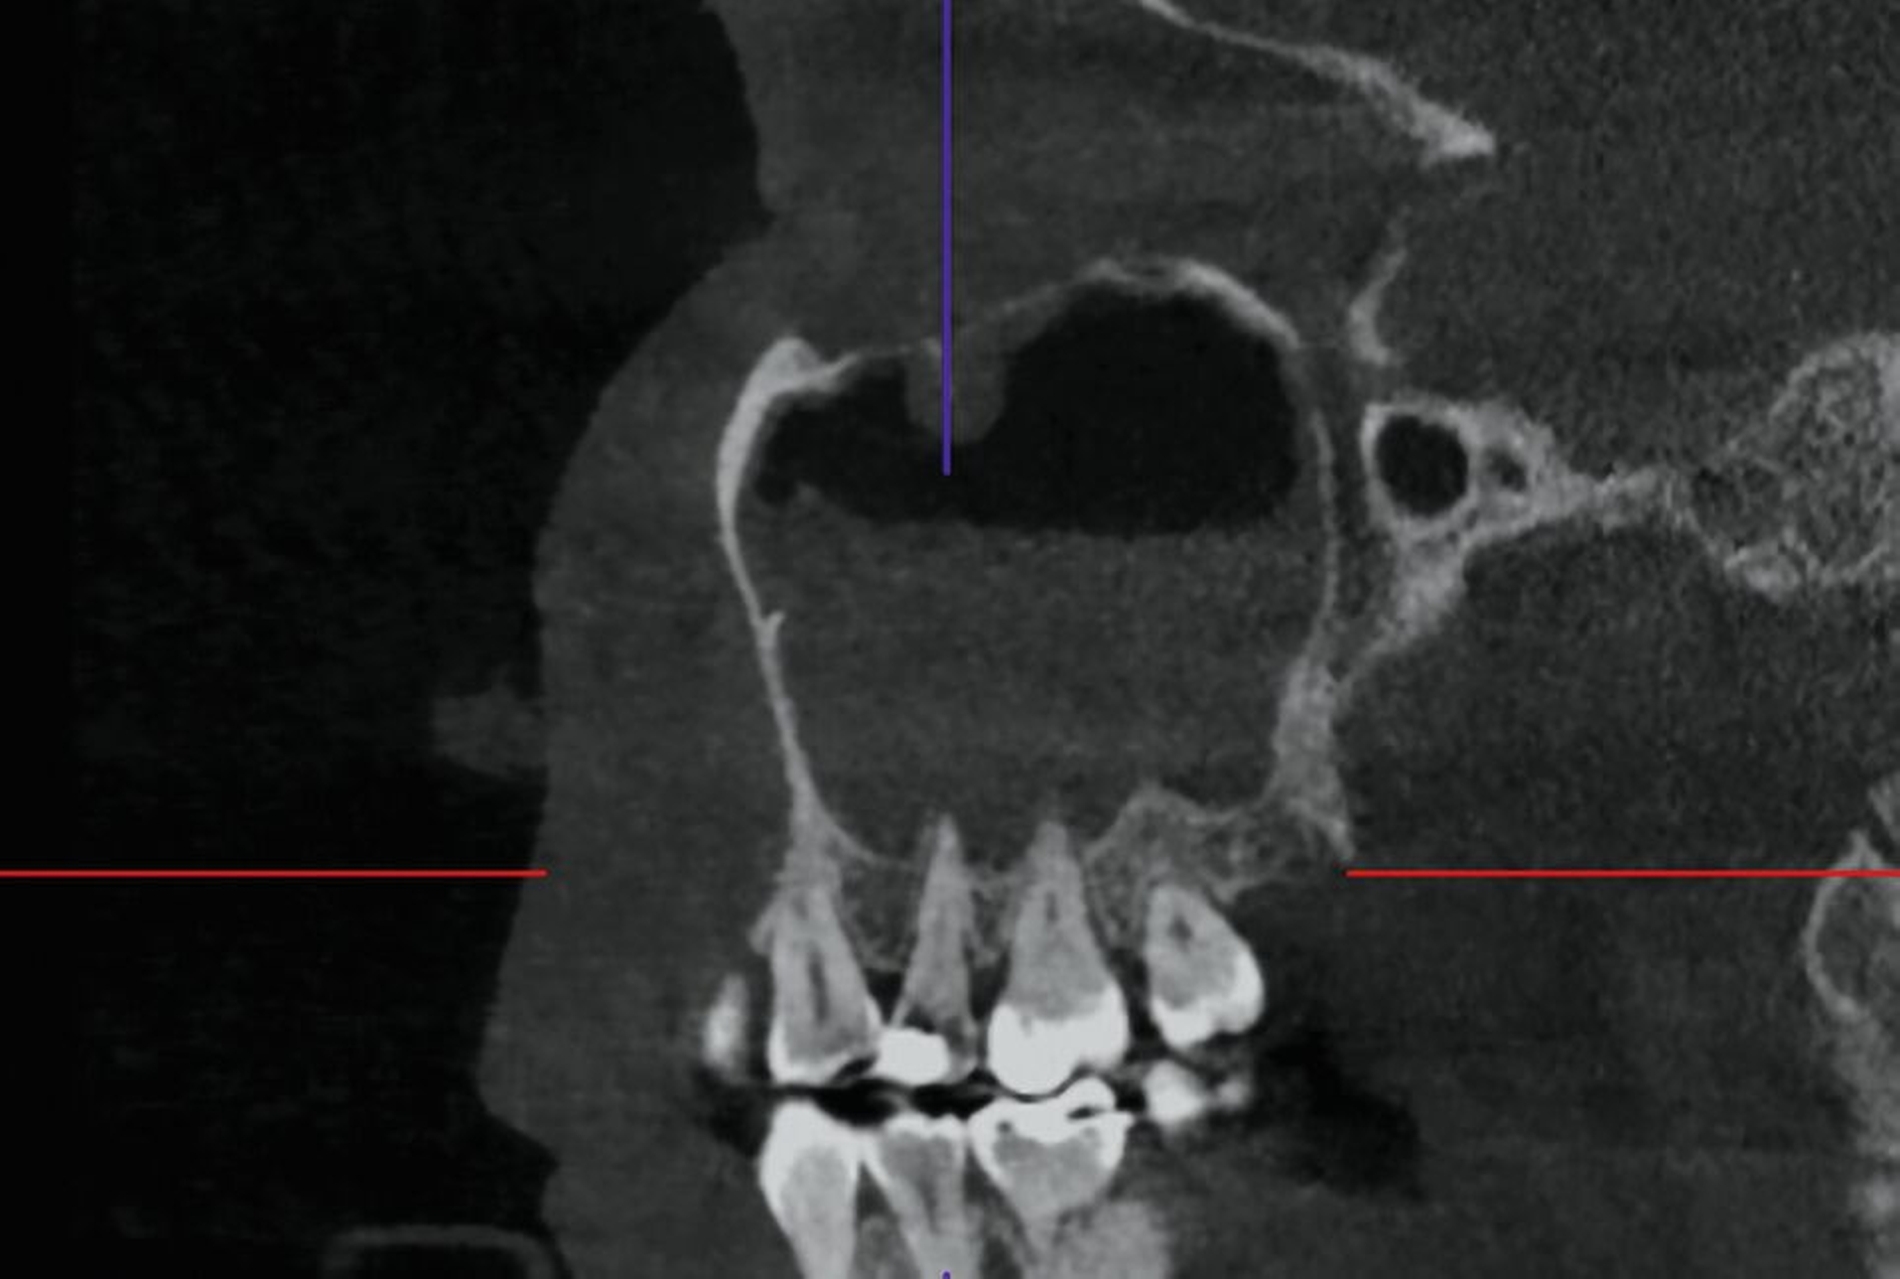

Das DVT zeigte eine Spiegelbildung im rechten Sinus maxillaris, jedoch keinen stark auffälligen knöchernen Befund (Abbildung 2). Die Patientin wurde zu intravenöser Antibiose, Analgesie und Ernährung über eine nasogastrale Sonde stationär aufgenommen. Im Verlauf wurde eine Verbandsplatte per Intraoralscan angefertigt und eine Operation zur Nekrosektomie und Wundanfrischung geplant. Zum Zeitpunkt des operativen Eingriffs hatten sich bereits Teile der vestibulären und der palatinalen Schleimhaut abgelöst. Nach Debridement zeigte sich ein großflächiges Areal mit freiliegendem Knochen. Der Zahn 15 wurde bei Lockerungsgrad III entfernt (Abbildung 3).